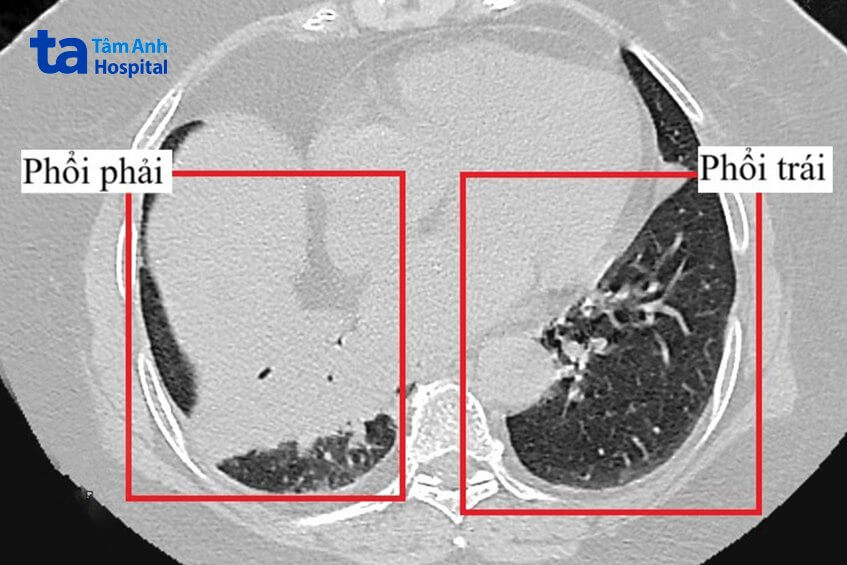

Người bệnh được đưa vào khoa Cấp cứu, BVĐK Tâm Anh TP.HCM trong tình trạng khó thở, sốt kèm ho đờm. Ngay lập tức, bác sĩ CKI Phan Tuấn Trọng đặt ống nghe kiểm tra phổi cho bệnh nhân. Bình thường khi ho cả hai nhánh phổi trái và phải đều có tiếng rít nhưng khi bà M. ho chỉ nghe tiếng rít ở vùng phổi phải. Nghi ngờ người bệnh có dị vật trong phổi, bác sĩ Trọng chỉ định cho bà M. chụp CT lồng ngực và xét nghiệm máu.

Đúng với chẩn đoán của bác sĩ Trọng, kết quả chụp CT cho thấy phổi bên phải của người bệnh có mảng viêm lớn, tràn dịch ít, tắc hoàn toàn nhánh phế quản phải. Xét nghiệm máu cũng ghi nhận bạch cầu tăng cao, oxy máu giảm nhẹ, điều này phù hợp tình trạng nhiễm trùng phổi. Kết quả cấy mủ cho thấy viêm phổi gây ra bởi tụ cầu Staphylococcus Aureus, người bệnh được sử dụng thuốc kháng sinh đặc hiệu điều trị loại vi khuẩn này. Người bệnh còn được dùng thuốc kháng viêm, giảm ho, thở oxy để điều trị viêm phổi, tràn dịch màng phổi, chờ thể trạng ổn định để nội soi phế quản gắp dị vật.